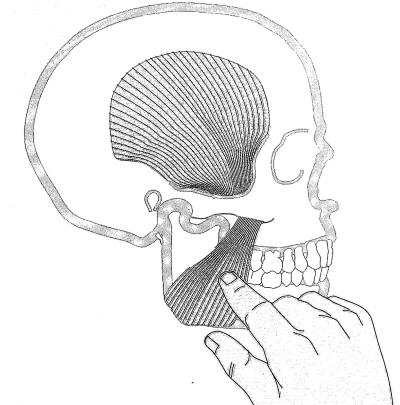

Palpación del haz inferior del pterigoideo externo: |

Para palpar el haz inferior del pterigoideo

externo, se realiza con el dedo meñique y se lo ubica por

delante del pilar anterior hasta la zona de tuberosidad. En

ese momento se desliza el dedo hacia atrás, con presión

moderada. El paciente puede sentir una molestia moderada,

hasta un dolor exquisito.

Si existe dolor intenso a la

palpación es señal de que el paciente presenta bruxismo. |